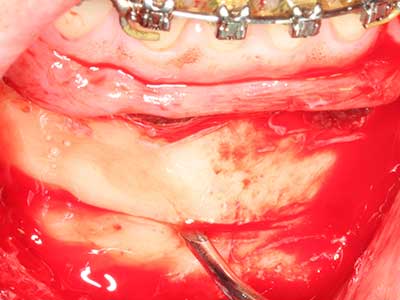

Knochengewebe ist nicht nur rein mineralisch, sondern auch in wesentlichen Anteilen aus Kollagenfasern aufgebaut. Dies gewährleistet neben einer guten Druckfestigkeit eine gewisse Flexibilität, welche für die Durchführung von Augmentationen genutzt werden kann. Bei der klassischen Expansionsplastik im Sinne eines Bone Splittings wird der atrophierte Kieferkamm in seiner Längsachse gespalten und nach Erreichen einer ausreichenden Osteotomietiefe vorsichtig aufgedehnt (Abb. 13-16), idealerweise ohne den Kiefer wesentlich zu deperiostieren (Brugnami, Caiazzo et al. 2014, Stricker, Fleiner et al. 2014). Bewährt haben sich Schrauben- und Plattensysteme mit zunehmender Expansionsdistanz, um die beiden Knochenlamellen unterhalb der Bruchschwelle voneinander zu distanzieren. In der Regel werden Restknochenbreiten von mindestens 3-4 mm gefordert (Chiapasco, Zaniboni et al. 2006), um eine ausreichende Flexibilität und knöcherne Bedeckung der einzubringenden Implantate zu gewährleisten. Ggf. kann eine ein- oder beidseitige vertikale Entlastungsosteotomie die Flexibilität verbessern. Als Alternative zur klassischen Technik wurde eine Kombination mit weiteren augmentativen Techniken vor allem auf der bukkalen Seite beschrieben.

Mittels Piezosägen erfolgt die Anlage des Splittings besonders schonend und ohne wesentliche Dimensionsverluste, so dass sich keine signifikanten Unterschiede von Implantaten im gesplitteten Kiefer im Vergleich zum nicht defizitären Alveolarkamm gezeigt haben (Chiapasco, Zaniboni et al. 2006, Danza, Guidi et al. 2009). Gerade beim lokal begrenzten und tiefen Splitting ist jedoch stets auf eine ausreichende Wasserkühlung zu achten, um thermische Belastungen in den apikalen Osteotomiebereichen zu vermeiden.